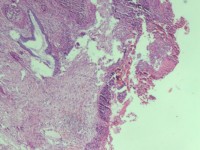

宫颈活检组织

性别

女

年龄

43岁

临床诊断

宫颈病变

一般病史

宫颈癌筛查:hpv16(+))

标本名称

宫颈组织

大体所见

灰白色组织

老师们看看,高级别累腺吗